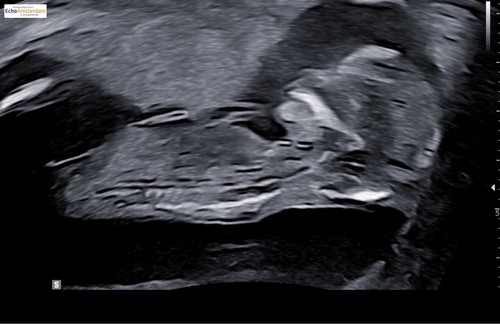

Hoihoi, dit heb ik laten doen, gewoon uit nieuwsgierigheid. Ik heb nog een foto, kan iemand zien of dit een beetje klopt ?

Hoihoi, dit heb ik laten doen, gewoon uit nieuwsgierigheid. Ik heb nog een ...

Deze